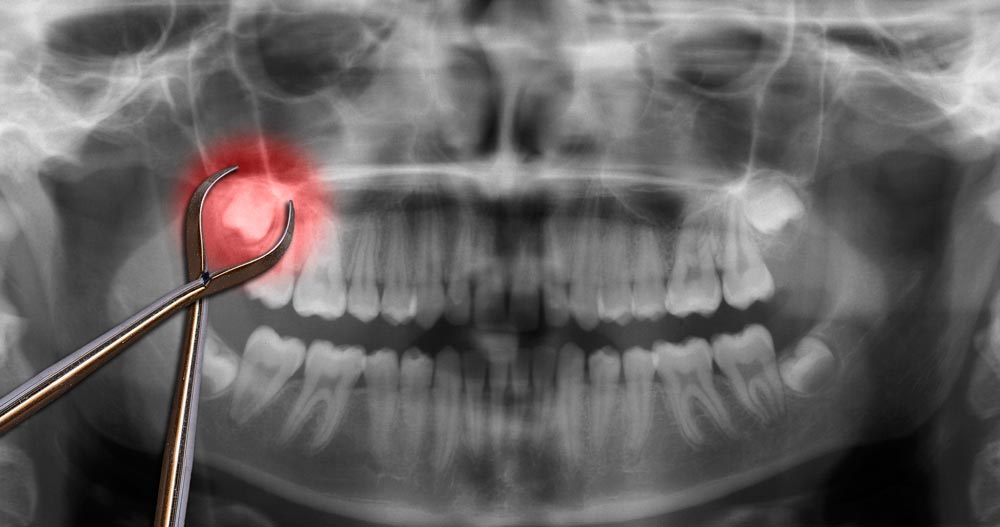

Dents de sagesse et extractionLes dents de sagesse sont les dents les plus éloignées au niveau de l’arcade dentaire de l’être humain et elles sont également les dernières à pousser. Vers 16 ans, votre dentiste évaluera à l’aide d’une radiographie panoramique si celles-ci auront la place nécessaire à érupter. Il arrive souvent qu’elles n’aient pas suffisamment d’espace pour sortir complètement. C’est dans ce cas de figure où les dents de sagesse demeurent incluses ou semi-incluses qu’une problématique se présentera. Votre dentiste vous proposera dans la majorité des cas de les extraire, dans le but de limiter les risques possibles tels que l’infection, la formation de kyste, la carie dentaire, le dommage aux dents adjacentes et la douleur. |